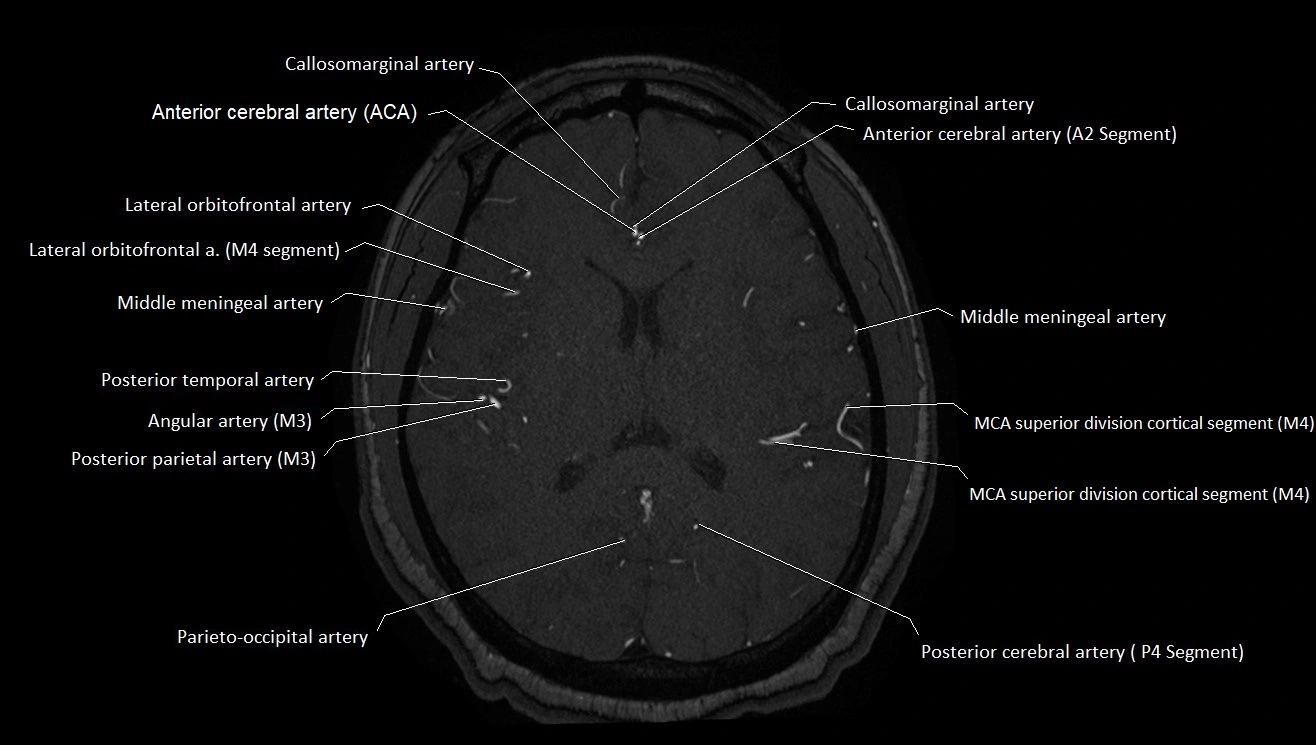

MRI images

image